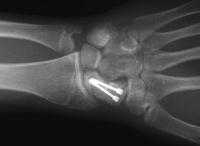

Healed.

The patient requested hardware removal prior to enlisting for military duty. Final films.